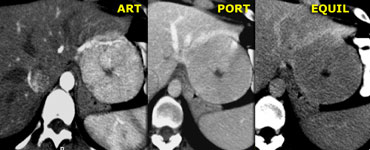

Typical hemangioma with nodular peripheral enhancement. Typical hemangioma with nodular peripheral enhancement.

Enhancement in Hemangioma

A hemangioma is a slowly perfused vascular space.

So the timing and amount of enhancement will follow, but lag behind the arterial system.

Hemangiomas less than 1 cm frequently demonstrate immediate homogenous enhancement, isodense to the aorta.

Hemangiomas larger than 1cm generally show slow centripetal spread of nodular enhancement, slowly decreasing in density.

On the left a typical hemangioma.

Enhancement in arterial phase is almost isodense to the aorta, and, as contrast diffuses toward the center of the lesion, the level of enhancement lowers slowly, and in the late phase is still hyperdense compared to the vascular spaces.